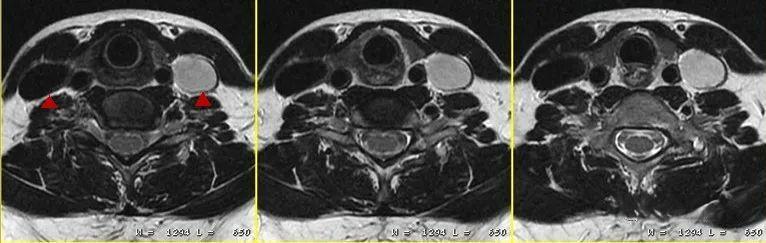

MRI技师的工作看似简单,实则暗藏玄机。作为一名经验丰富的MRI技师,我想分享一些在日常工作中容易被忽视,但却至关重要的细节。这些细节可能不会在教科书中明确指出,却是保证图像质量、提高诊断准确性的关键所在。